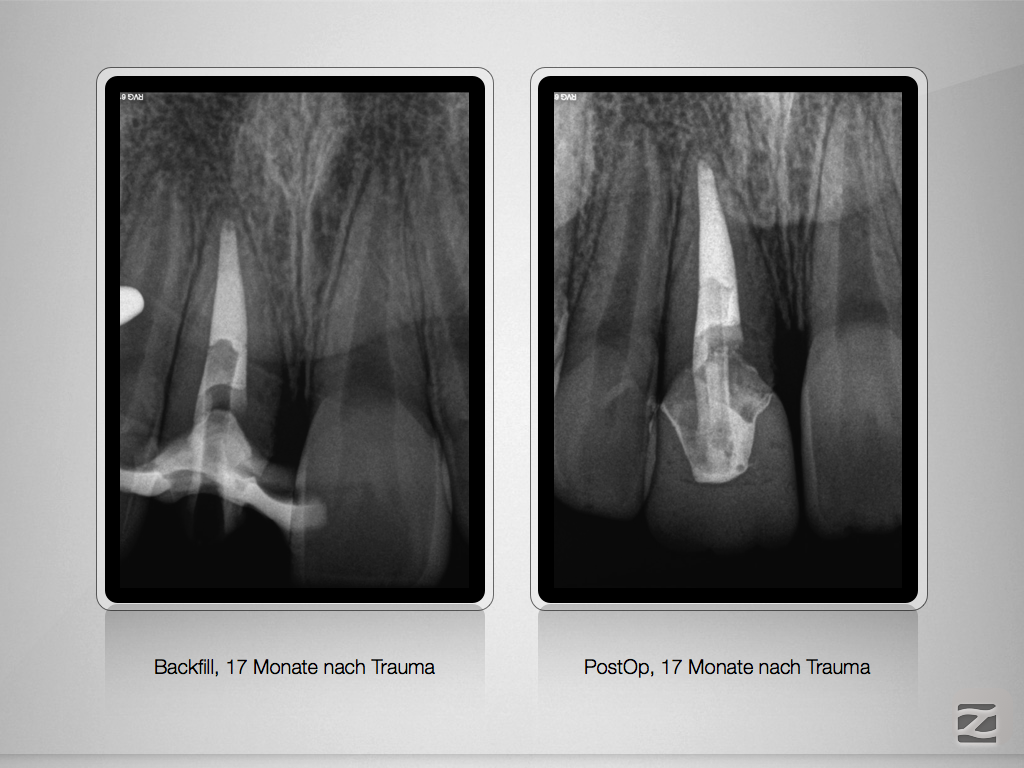

11D.011

Komplizierte Kronen-Wurzelfraktur